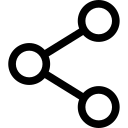

Once the tibial nerve has been identified, the CPN is visualized slightly more superficial and lateral to the tibial nerve. The transducer should be slid proximally until the tibial and peroneal nerves are visualized coming together to form the sciatic nerve before its division (Figure 4). This junction usually occurs at a distance 5–10 cm from the popliteal crease but may occur very close to the crease or, less commonly, more proximally in the thigh.

FIGURE 4 Sonoanatomy of the sciatic nerve (ScN) before its division. Shown are the ScN, superior and lateral to the popliteal artery (PA), positioned between the biceps femoris muscle (BFM) the semimembranosus muscle (SmM), and the semitendinosus muscle (StM).

As the transducer is moved proximally, the popliteal vessels move deeper and become more challenging to image. Adjustments in depth, gain, focus, and direction of the US beam should be made to keep the nerve visible at all times. At the popliteal fossa, the sciatic nerve typically is visualized at a depth of 2–4 cm.